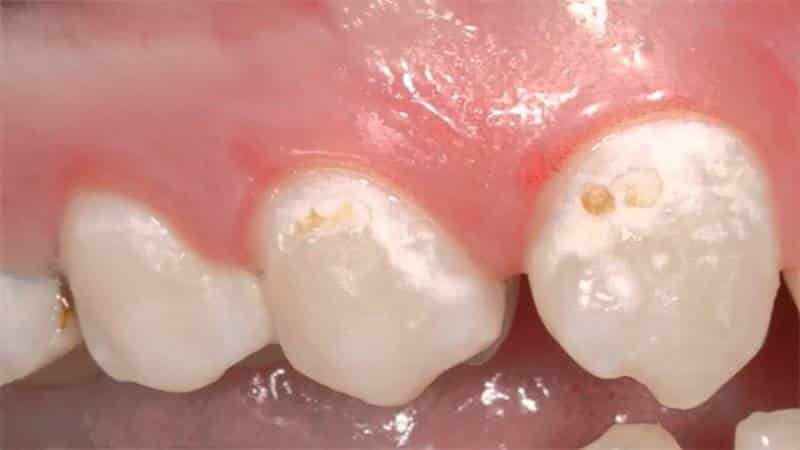

Кариес. Если зубной камень удалось удалить, то это можно сделать с помощью ультразвуковой чистки или других стоматологических процедур.

Однако если темное пятно не поддается механическому воздействию, возможно, у вас развился кариес, который приводит к разрушению зуба под воздействием соляной кислоты, выделяемой кариозными бактериями. В этом случае потребуется лечение и пломбирование у стоматолога.